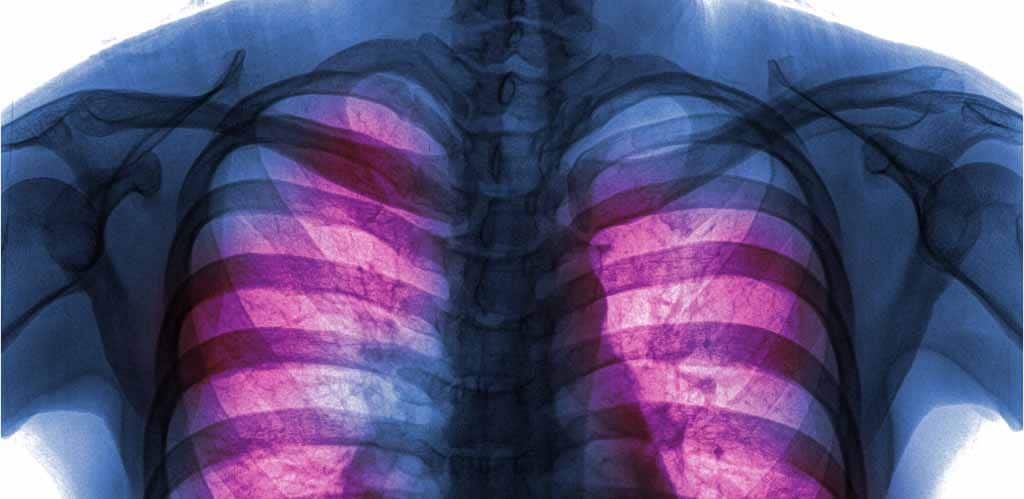

Tuberculosis (TB) is an airborne (spread by water droplets from the infected person) mycobacterial disease which often affects the lungs but can also involve other organs like the brain, kidneys and bone.

The simplest test for TB is the Mantoux test where a small injection is made in to the forearm with tuberculin purified protein derivative (PPD). This is assessed two to three days later by the doctor to see if there is a reaction indicating previous exposure to TB. Chest x-rays are also sometimes used for assessment. The most accurate test is a blood test called the Quantiferon-TB Gold test. It does not require a second visit to the doctor but is relatively costly.